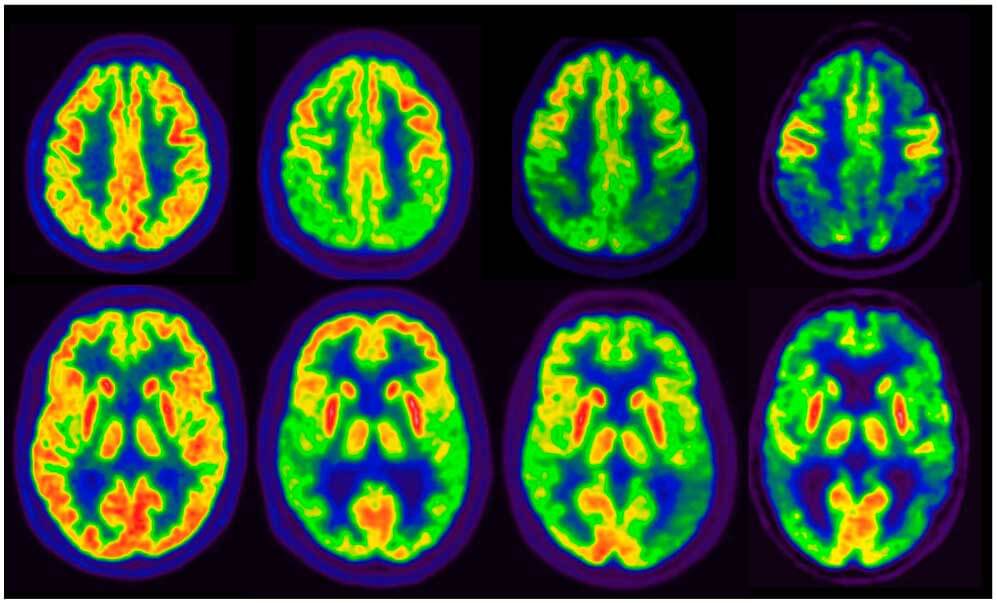

En un estudio observacional de gran tamaño se observó que la tasa de PET cerebral positivo para tau alcanzaba un 10%  en individuos sin deterioro cognitivo, y la combinación de positividad para PET de amiloide beta (Aβ) y tau se asoció con un alto riesgo de progresión clínica, tanto en la etapa preclínica como en la sintomática de la enfermedad de Alzheimer. Estos hallazgos subrayan el potencial de la PET para tau como biomarcador para la estadificación de la enfermedad. JAMA, 16 de junio de 2025.

La tomografía por emisión de positrones de amiloide produce un incremento del tratamiento de pacientes con deterioro cognitivo leve o demencia

JAMA, 2 de abril 2019el manejo del paciente 90 días después de la PET amiloide (en comparación con el plan pre-PET) cambio en el 60,2% de los pacientes con deterioro cognitivo leve y el 63,5% de los pacientes con demencia.